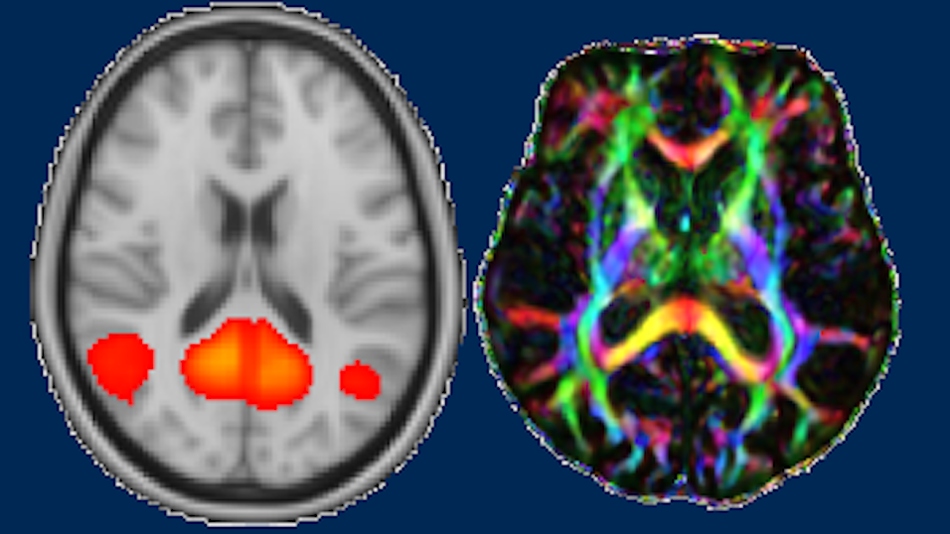

Anhand unseres Forschungsprojekts kann man erfahren, wie positive und negative Kindheitserfahrungen mit verschiedenen Aspekten der psychischen und biologischen Gesundheit zusammenhängen. Zudem gibt es die Möglichkeit, das Gehirn interaktiv durch MRT-Neuroimaging und 3D-Modelle kennenzulernen. Die MRT ermöglicht einen nicht-invasiven und detaillierten Einblick in die Anatomie, die Aktivierungen sowie strukturellen und funktionellen Verbindung des Gehirns, die mit Emotionen und psychischer Gesundheit in Verbindung gebracht werden können.